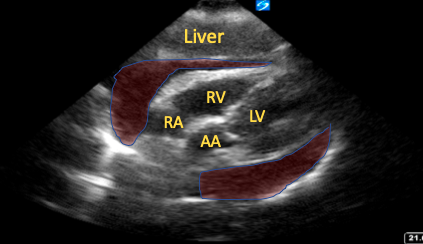

The SC window provides a global view of the pericardial sac, in more than one plane, and is easily accessible. Its ability to clearly visualize the right ventricular free wall allows for the detection of anterior pericardial effusions that are often not well visualized in other windows and signs of tamponade, such as chamber collapse (Figure 1).15

Figure 1. Subcostal four-chamber view with a large pericardial effusion (shaded red areas) and right atrial collapse visible.

RA=right atrium, RV=right ventricle, LV=left ventricle, AA=ascending aorta